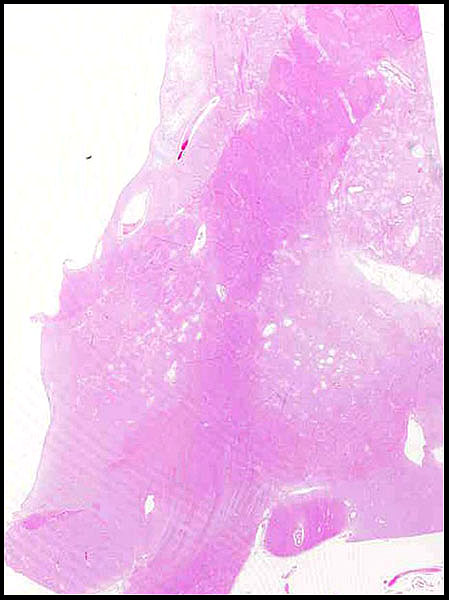

Arteriosclerosis del Polígono de Willis